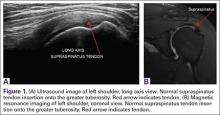

Ultrasound is similar to MRI as it images tissues and gives us ideas whether that tissue is normal, damaged, or diseased (Figures 1A, 1B). MRI is based on magnetics and large machines that cannot be moved. MRI yields planar images that can only be changed by changing the position of the limb or body in the MRI tube. This can create an issue with obese patients or with postoperative patients who cannot maintain the operated body part in one position for the length of the MRI scan. Ultrasound is better tolerated by patients without the need for claustrophobic large machines (Table 1). In 2004, Middleton and colleagues7 surveyed 118 patients who obtained an ultrasound and MRI of the shoulder for suspected rotator cuff pathology; ultrasound had higher satisfaction levels, and 93% of patients preferred ultrasound to MRI.